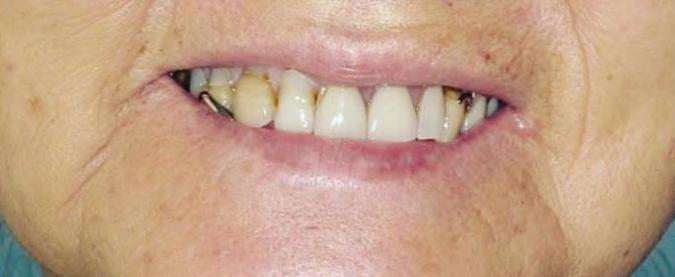

By Karl A. Smith, DDS, MS ditions

A smile is the first impression that communicates a woman’s happiness and confidence; if you wish to keep your winning smile out in front, you will want to take special care of what’s behind it – your periodontal (gum) health.

Periodontal health is connected to a woman’s overall health. As your health care needs change throughout your life, during puberty, pregnancy, and menopause, your oral care needs may change.

Hormonal fluctuations during these times may affect your gum tissue and the underlying bone that support your teeth. These changes may increase your susceptibility to periodontal disease and require you to take special care of your oral health.